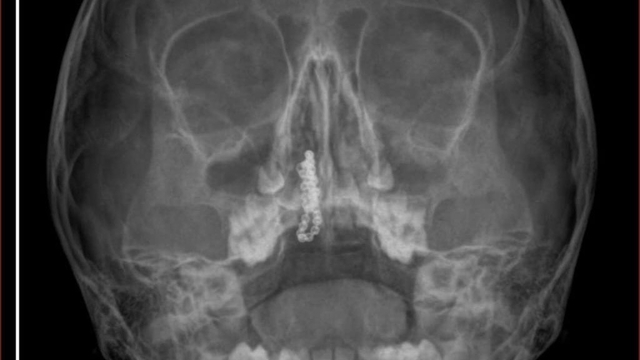

Kentte yaşayan Gökhan-Nalan Tekin çifti, yaklaşık 4 ay önce şiddetli burun kanamasının yanı sıra akıntı şikayetleriyle kızları Polen'i, bir özel hastaneye götürdü. Burada röntgeni çekilip, tetkikleri tamamlanan küçük kıza, iddiaya göre enfeksiyon teşhisi konulup, ilaç verildi. Eve dönen aile, kanama ve akıntının geçmemesi üzerine bu kez Rize Devlet Hastanesi'ne giderek Kulak Burun Boğaz Polikliniği'ne başvurdu. Devlet hastanesindeki doktorun incelemesi ve kapsamlı röntgen çekilmesi sonrası Polen'in burnunda metal cisim olduğu fark edildi. 2 yıldır burunda kaldığı değerlendirilip, küçük top şeklinde tırnak makası zinciri olduğu belirlenen cisim, başarılı ameliyatla çıkarıldı. Bir süre tedavisi sürdürülen Polen, sağlığına kavuşunca taburcu edildi. Özel hastane yetkilileri, konuyla ilgili açıklama yapmazken; aile suç duyurusunda bulunacaklarını söyledi.

Kızının burnundan sürekli siyah renkte akıntı olduğunu anlatan Gökhan Tekin, "Çocuğumun burnundan kanama ile sürekli siyah akıntı geliyordu. Özel hastaneye götürdüm. Özel hastanede film çekildi, hiçbir bulguya rastlanılmadığı söylendi. O siyah leke de enfeksiyona dayalı olan bir şey olduğu bize söylendi. Eve geldik, akıntı sürmesi üzerine bu kez devlet hastanesine başvurduk. Burunda metal zinciri fark ettiler. Böyle bir ihmalkarlık olabilir mi? Özel hastaneye gidiyoruz, paramızla rezil oluyoruz. Zincir, 2 yıldır burnunda ve devletimizin hastanesinde iyi bir doktorumuz zinciri ortaya çıkarıyor, kızım ölümden dönüyor. Ben sonuna kadar bu işin peşini bırakmayacağım. Sonuna kadar hukuk mücadelesi vereceğim. Bu da diğer hastalarımıza ibret olsun. İşte, bakın koca bir zincir. 'Bulguya rastlanılmadı' deniliyor" dedi.

Kızının ameliyat sonrası durumunun iyi olduğunu söyleyen Tekin, "İnanır mısınız bize 'Evde soba mı yanıyor? Acaba kömür isten dolayı mıdır bu?' dendi. Böyle bir şey olabilir mi? Ameliyattan çıkan parmağım kadar zincir. Devlet hastanesindeki doktor da 'Bu nasıl gözden kaçılabilir? Böyle bir pozisyon nasıl görülmeyebilir?' yorumunda bulundu. Allah'a şükür olsun atlattık. Şu anda durumu, vaziyeti iyidir. Ben şuna inanıyorum doktor da bir şans işidir. Bakın paramızla özele gideriz ya hani bizde, daha iyi ilgilenirler. Oysa devlet hastanesindeki doktorumuz olayı meydana çıkardı" diye konuştu.